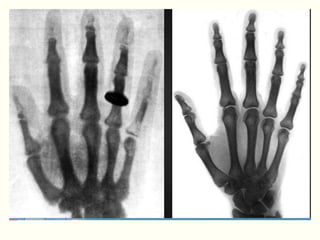

IMAGEM RADIOGRÁFICA

 Imagem produzida sobre uma

emulsão fotográfica

 Áreas escuras – radiotransparentes

 Áreas claras – radiopacas

IMAGEM RADIOGRÁFICA  Imagemproduzida sobre uma emulsão fotográfica  Áreas escuras – radiotransparentes  Áreas claras – radiopacas